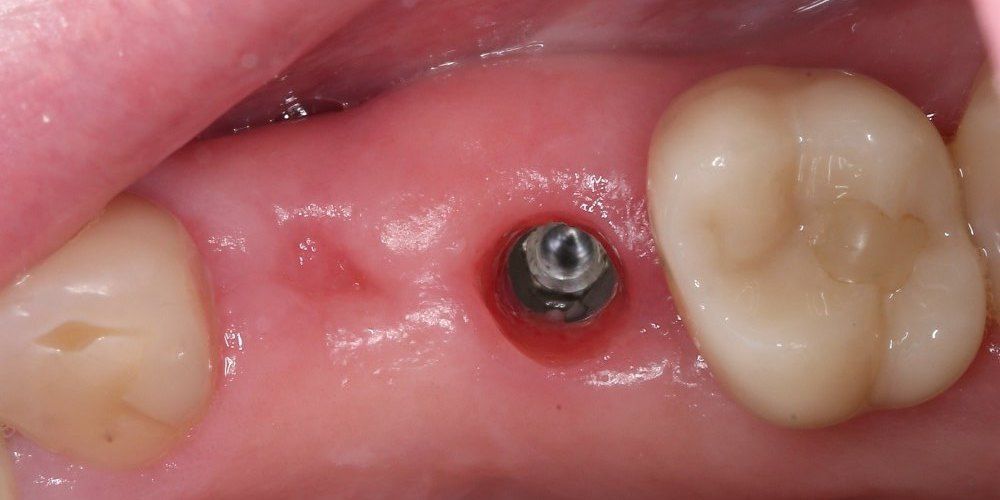

Имплантация жевательных зубов,

это самая востребованная операция.

после

до